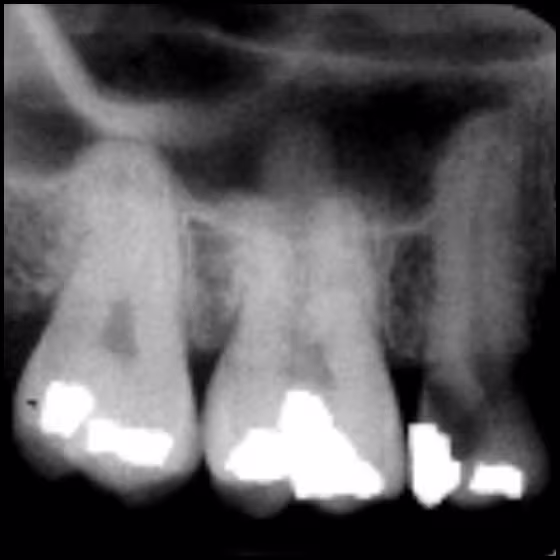

This course will focus on the anatomical structures that are recorded on intraoral radiographic images. The clinician must be familiar with the anatomical structures to ensure accurate orientation and/or arrangement prior to interpretation. Recognition of anatomical structures serves as a baseline to differentiate normal structures from abnormalities.

- Identify anatomical structures that are commonly recorded on bitewings.